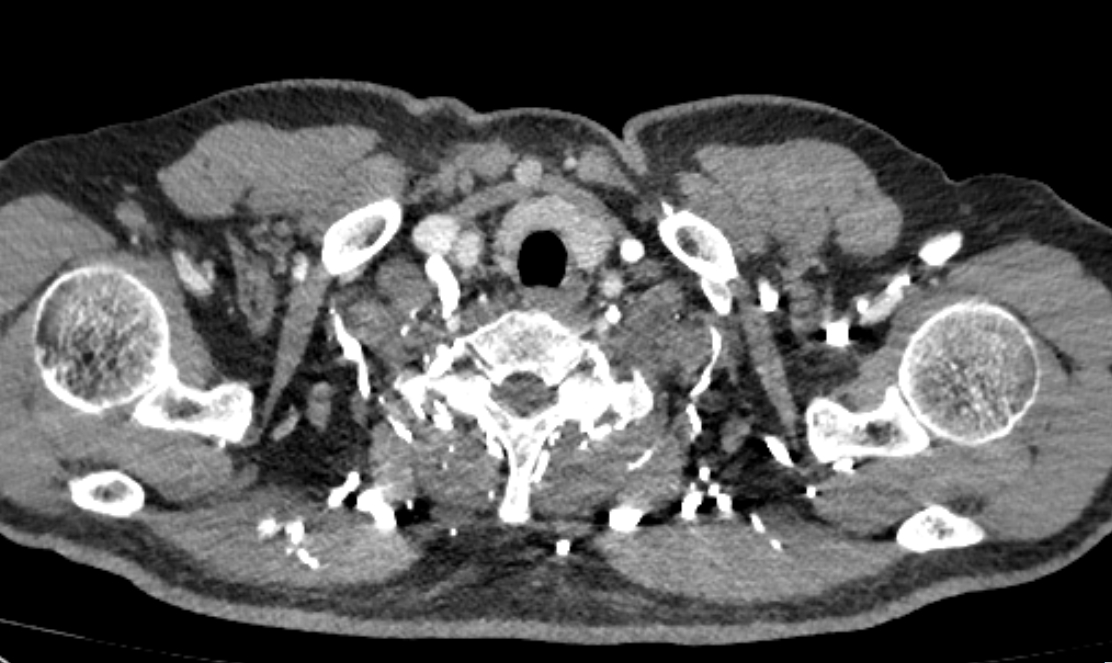

右锁骨下堵塞导致肺动脉充盈欠佳

改左手注射 肺动脉充盈理想